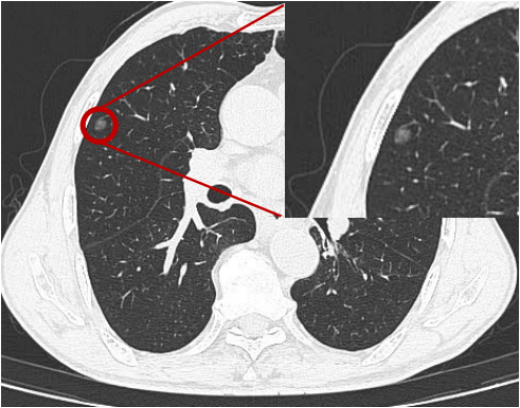

CT、核磁的影像不是一张图,而是成百上千帧的“连续画面”(比如胸部CT可能有几百或者几千层)。影像科医生要一帧帧看,哪怕是比芝麻还小的病灶(比如肺部3毫米的微小结节、肝脏里的小囊肿),也得揪出来。

例如一位患者咳嗽很久,影像科医生看CT可以精准指出“炎症在右肺下叶,是局限性小病灶”。这种能力源于其对解剖学、病理学的深入理解,以及长期训练练就的“火眼金睛”。

影像科医生判读影像不能仅看画面,还需结合临床信息。如肺部阴影,年轻人多为普通炎症,老年人有吸烟史则需警惕;肝脏小肿块,需区分患者有无乙肝病史。发现肺部结节时,会结合年龄、吸烟史、家族病史等,排除假阳性、避免误判,精准判断结节性质。